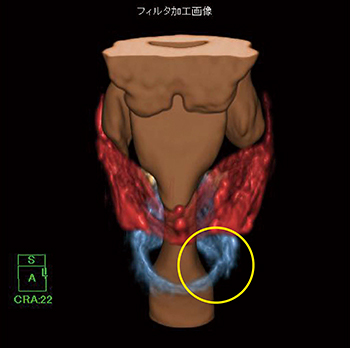

そこで,3Dフィルタを使用してオリジナル画像のノイズを低減させて,ボリュームの辺縁を滑らかに表示させる処理を行った。調整率によってフィルタのかかる割合が細かく設定でき,容易に画像確認を行うことが可能である(図5)。3Dフィルタによりノイズが低減されて辺縁が滑らかになったことで,輪状軟骨の左側壁部の骨折がより明瞭になり,内側に偏位しているのが確認できる(図6)。

図6 3Dフィルタを使用した喉頭軟骨VR画像